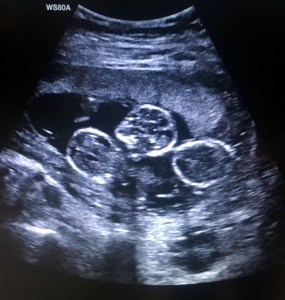

14 Week Ultrasound